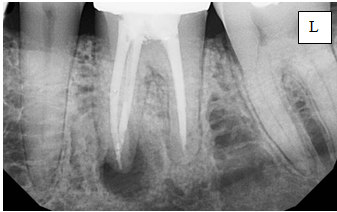

5.Назовите снимок, опишите 3.6 зуб.

5. Внутриротовой дентальный снимок 3.6

6. Антиретровирусная терапия. удаление зуба 3.6. Патогенетическая терапия кандидоза, противогрибковые средства.

4.Назовите снимок, опишите 3.6 зуб.

4. Внутриротовая дентальная рентгенограмма зуба 3.6